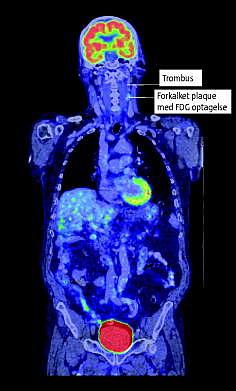

Positronemissionstomografi/computertomografi (PET/CT) anvendes ved stadieinddeling af hoved/halskræft og viste metabolisk aktiv sygdom disse steder.

Patienten var blind på venstre øje pga. en blodprop og var i warfarinbehandling. PET/CT udført med intravenøs-kontrast viste som bifund en trombe i venstre arteria carotis interna og 2-[18 F]-fluoro-2-deoxy-D-glukose (FDG)-akkumulerende plaque over carotisbifurkaturen.

FDG-optagelse i plaques er direkte relateret til makrofagindhold, som er årsag til plaqueinstabilitet. Statiner fremmer plaquestabilitet ved sænkning af makrofagindhold og aktivitet. Patienten fik statinbehandling.

Konklusion: FDG-PET kan have en vigtig rolle i identificering af vulnerable plaques. PET/CT med intravenøs kontrast viste her et væsentligt tilfældigt fund: FDG-akkumulerende plaque og trombe i arteria carotis interna, som kan forklare blindheden på øjet.